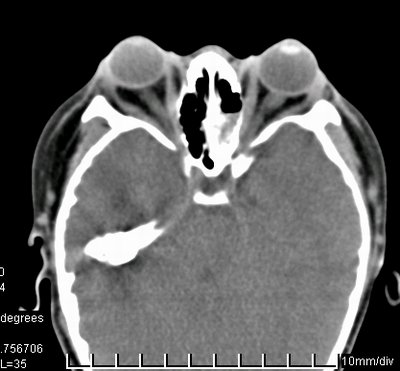

儿子的CT扫描

Crouzon综合征,有名颅面骨发育不全(Craniofacial dysostosis),1912年由法国医生Crouzon首次报道,是颅骨骨缝早闭所致。外国文献报道,患病率1/3000。 临床表现:突眼、眼眶浅、“鹦鹉鼻”、反咬颌、鼻咽狭窄、视神经孔窄、头颅畸形。可同时伴视神经萎缩、青光眼、白内障。 分子遗传学:成纤维细胞生长因子受体基因突变,常染色体显性遗传,可由新发突变导致。 我院眼科拟行分子遗传学研究(欢迎外院病人加入)。脑外、整形、口腔、眼科讨论手术方案。